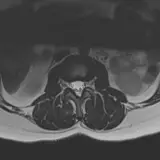

Over 2,100 interactive radiology cases, curated by radiologists for your level of training. Scroll, window, and view cases full screen โ€” just like on PACS. Click linked findings in each writeup to jump straight to them on the image. Cases include sample reports, a focused discussion section, original illustrations, and videos.

Casi completamente interattivi con gli strumenti che ti aspetti su un PACS: scroll, windowing, zoom, pan, misurazioni, ROI e modalitร  a schermo intero.

Annotazioni dettagliate evidenziano i reperti chiave direttamente sui casi. Clicca sui reperti collegati nella descrizione del caso per saltare alla loro esatta posizione sullo scan.